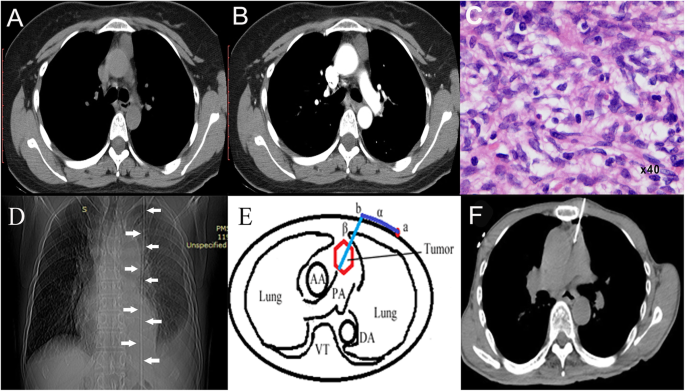

Puncture paths design

The RFA procedure was performed under CT guidance. The RFA path was designed through the preoperative plain CT images according to the tumor position. The anterior approaches were generally selected in a lateral position or supine position. The tract passed through the chest wall and/or partial peripheral lung tissue to reach the thymus mass without passing through any vessels and nerves (Fig. 1). This procedure requires accuracy to minimize the possibility of damage to the major vessels, principal bronchus, and nerves along the puncture pathway.

Puncture pathway design. a, b and c are preoperative CT images for mapping the mass and the related structure around the mass. a is a plain CT scan. b is the arterial phase of the scan, while c is in the venous phase of the scan. After mapping the mass, an imaging marker was placed on the surface of the body (white arrows in d, denoted by a in the transverse section). Illustration of the design process for the puncture approach (light blue line, denoted by β) and calculation of the insertion site (red point, denoted by b) is shown in e. The blue line between a and b is the distance from the imaging marker (a) to the insertion site (b). β is the depth of the puncture into the tumor (red hexagon). To ensure complete ablation, a sufficient puncture depth into the mass was essential. After careful design and step-by-step insertion, the radiofrequency probe (white line) was finally placed at the planned position in the tumor (f)

The entire procedure was performed on a 16-slice PHILIPS Brilliance TM Big Bore CT scanner (Koninklijke Philips N.V., Amsterdam, Netherlands). Before the operation, patients were placed on the CT bed in a lateral or dorsal position. When the position was confirmed, the patient remained still during the procedure for an accurate puncture. A slim galvanized wire was applied on the surface of the skin along the body as an imaging marker. The wire was used to locate the puncture (white arrows, D in Fig. 1) since the wire is visible on CT images. A plain CT scan was performed to locate the mass and design the puncture pathways with the help of the imaging marker. To clearly visualize the vessels that were involved within the procedure area, it was essential to intravenously inject a contrast agent. Sequential scanning, for both plain and contrast-enhanced CT scans, was performed using a 5 mm slice thickness and slice gap. With a similar method, the operator designed the puncture pathway of the monopolar RFA probe (17-15s30F, STAR med Co., Ltd., GYEONGGL-DO, Korea) and marked the puncture site on the skin (Fig. 1).